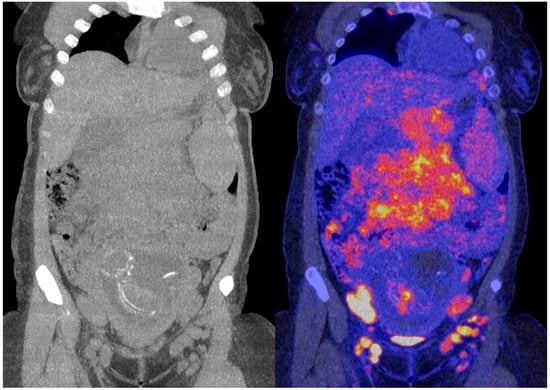

2. Case Presentation